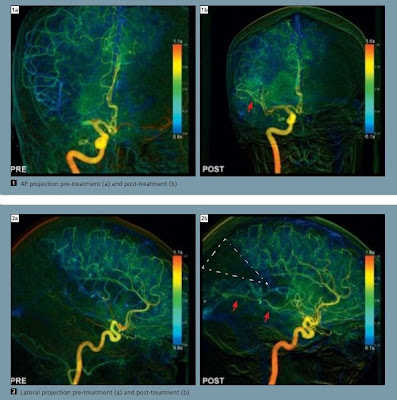

Siemens estabelece um novo padrão na subtração angiografiaO novo pedido syngo iFlow da Siemens Healthcare torna possível pela primeira vez de demonstrar uma completa ANGIOGRAFIA DE SUBTRAÇÃO DIGITAL (DSA) em uma seqüência única imagem colorida. Anteriormente, múltiplas sequencias de imagens em preto e branco teriam que ser revistos para a visualização do fluxo sangüíneo através dos vasos. Agora, com as cores do syngo iFlow a representação de contraste desde sua introdução nos vasos sanguíneos até toda a contrastação de todo o trajeto pode ser exibido em uma imagem.